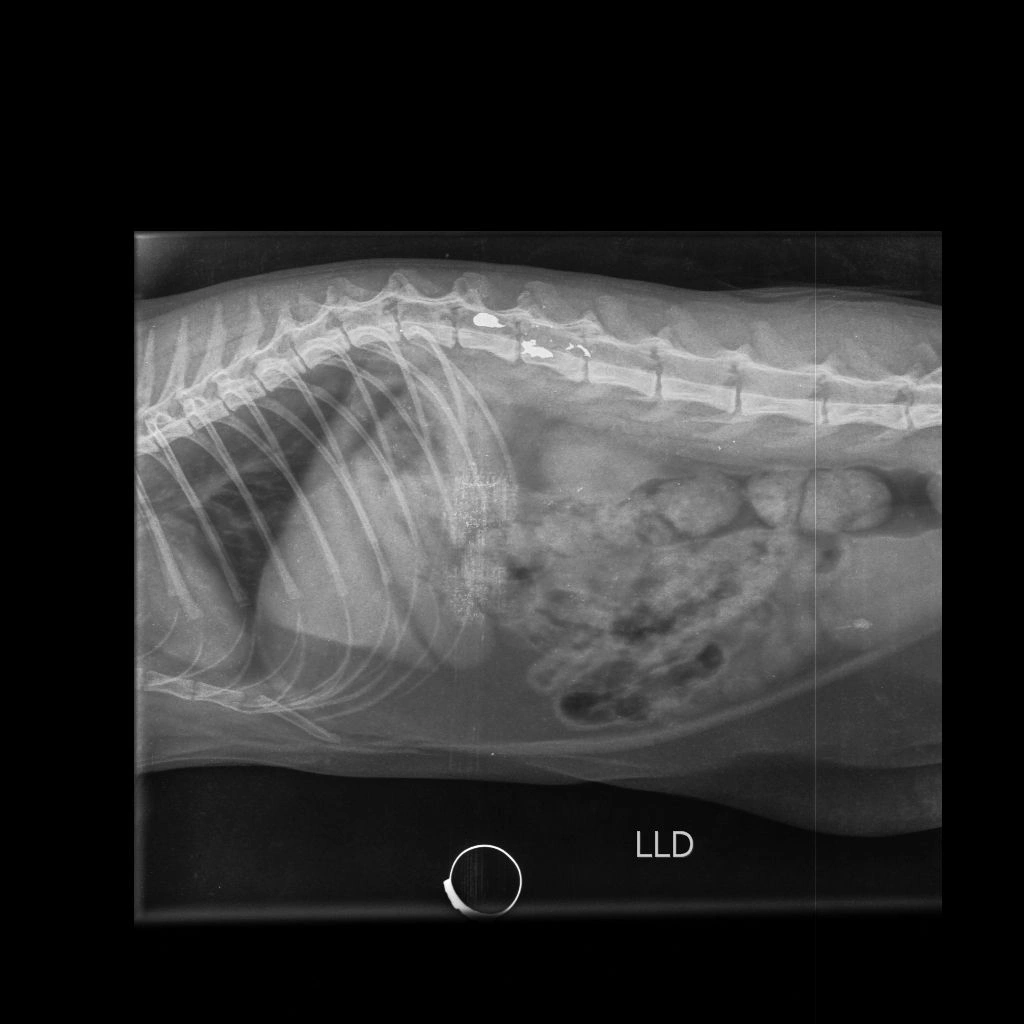

A gata, chamada Morgana, está sob os cuidados da clínica veterinária Vida Pets. De acordo com os responsáveis pelo animal, ela encontra-se estável e passa por exames antes da cirurgia. Os tutores já prestaram depoimento à Polícia Civil e afirmaram que irão acompanhar o caso até o fim. A família também agradeceu a mobilização da comunidade.

O caso veio à tona após a Polícia Militar do Paraná (PMPR) ser acionada via 190. Conforme relato do tutor, ele estava no pátio da residência com a esposa, por volta das 18h00, quando ouviu um estampido. Em seguida, a gata, que estava sobre o muro da casa, caiu ferida. O animal apresentava lesão compatível com projétil, embora inicialmente não fosse possível identificar se o disparo partiu de arma de fogo ou arma de pressão.